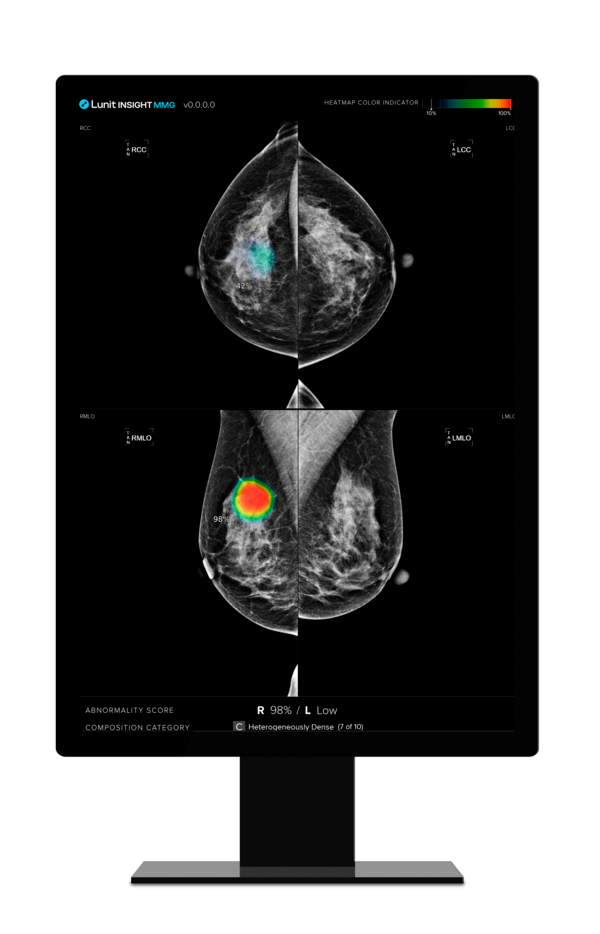

루닛 유방촬영술 AI 영상분석 솔루션 '루닛 인사이트 MMG./루닛 제공

[한스경제=김동주 기자] 의료 인공지능(AI) 기업 루닛은 유방촬영술 AI 영상분석 솔루션 ‘루닛 인사이트 MMG’의 유방암 조기 발견 및 의료진 업무 경감 효과를 입증한 유럽 연구 2건이 세계적 권위의 의학 저널에 게재됐다고 23일 밝혔다.

AI는 각 유방에 0부터 100까지의 점수를 부여하는데 점수가 높을수록 유방암 가능성이 높음을 의미한다. 연구 결과 나중에 암이 발견된 유방과 그렇지 않은 반대쪽 유방 사이의 평균 AI 점수 차이가 시간이 지남에 따라 증가했다. 이 차이는 첫 번째 검진에서 평균 21.3점, 두 번째 검진에서 30.7점, 세 번째 검진에서 79.0점으로 크게 증가했다. 반면, 유방암이 발생하지 않은 여성들의 경우 양쪽 유방 사이의 점수 차이가 모든 검진에서 10점 이하로 낮게 유지됐다.